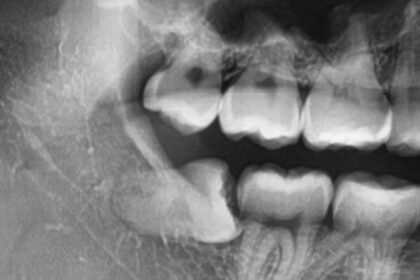

親知らずは一番奥に生えているため、歯ブラシが届きにくく、非常に虫歯になりやすい歯です。問題はそれだけではありません。親知らずが斜めに生えていると、手前の健康な歯(第二大臼歯)との間に食べかすが詰まりやすくなり、手前の歯まで虫歯にしてしまうことが少なくありません。

手前の歯は、親知らずがなければ虫歯にならなかったかもしれません。大切な歯を守るためにも、リスクのある親知らずは早めに抜歯することが推奨される場合があります。研究によれば、症状がないまま放置された親知らずも、時間の経過とともに虫歯や歯周病になる確率が高まることが示されています (Ghaeminia, Nienhuijs and Toedtling, 2020)。

レントゲン写真で、将来的に問題を起こす可能性が高いと判断された